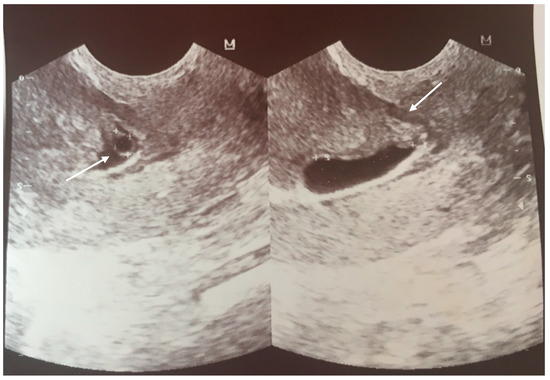

1.1. Case 1

1.2. Case 2